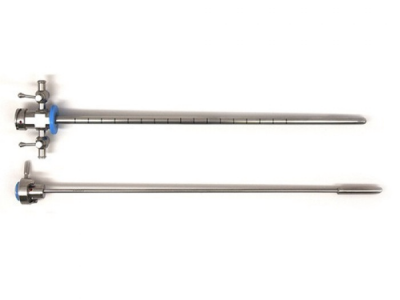

Nefrolitotomía Percutánea Con técnica Miniperc

Miniperc, es una técnica eficaz y segura, con una mínima incisión en la piel, para el tratamiento de las piedras en el riñón de pequeño y mediano tamaño.

El riesgo de sangrado, las posibles complicaciones y el tiempo de hospitalización es menor que con otras técnicas de nefrolitotomía percutánea.

Los calibres de los tractos de acceso se alejan considerablemente del calibre de la cirugía percutánea clásica, disminuyendo asi los daños generados en el parénquima renal.

El nefroscopio minipercutáneo es recomendable para el tratamiento de piedras de 1 hasta 3 cm, tiene un canal de trabajo que permite el paso de instrumentos de hasta 6.7 french.

Su diseño compacto y la ventaja de realizar incisiones mas pequeñas permiten una recuperación mas rápida y la reducción de complicaciones postoperatorias.

Tras la incisión cutánea, se ensancha el acceso con un solo dilatador hasta el punto de que la vaina se pueda deslizar hasta el riñón, ya no es necesario recurrir a los dilatadores telescópicos o los dilatadores de varios tamaños.

La miniperc implica, además de la reducción del diámetro del tracto externo y del instrumento de trabajo (nefroscopio), otras modificaciones en la técnica de la litotricia en beneficio de la comodidad postoperatoria del paciente.

Entre estas modificaciones se encuentran el uso de tecnología láser para la fragmentación o pulverización de cálculos, la disminución de los elementos de extracción, la reducción del calibre de la nefrostomia (abertura desde el exterior del cuerpo hasta la pelvis renal) y diferente estrategia de salida.

Nefroscopio

Telescopio Panoview con ocular desplazado lateralmente, dirección de visión de 12° y canal de trabajo de 6 Fr.